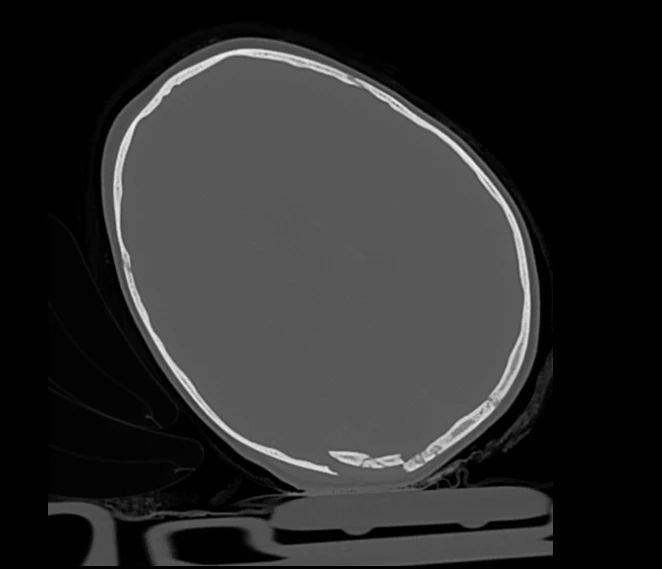

Малыш получил сочетанную травму: черепно-мозговую и перелом бедренной кости. Сейчас он в крайне тяжёлом состоянии находится в отделении анестезиологии и реанимации Детской республиканской клинической больницы.